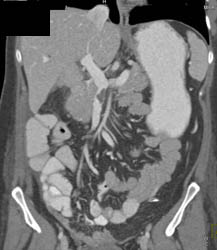

Chronic Pancreatitis